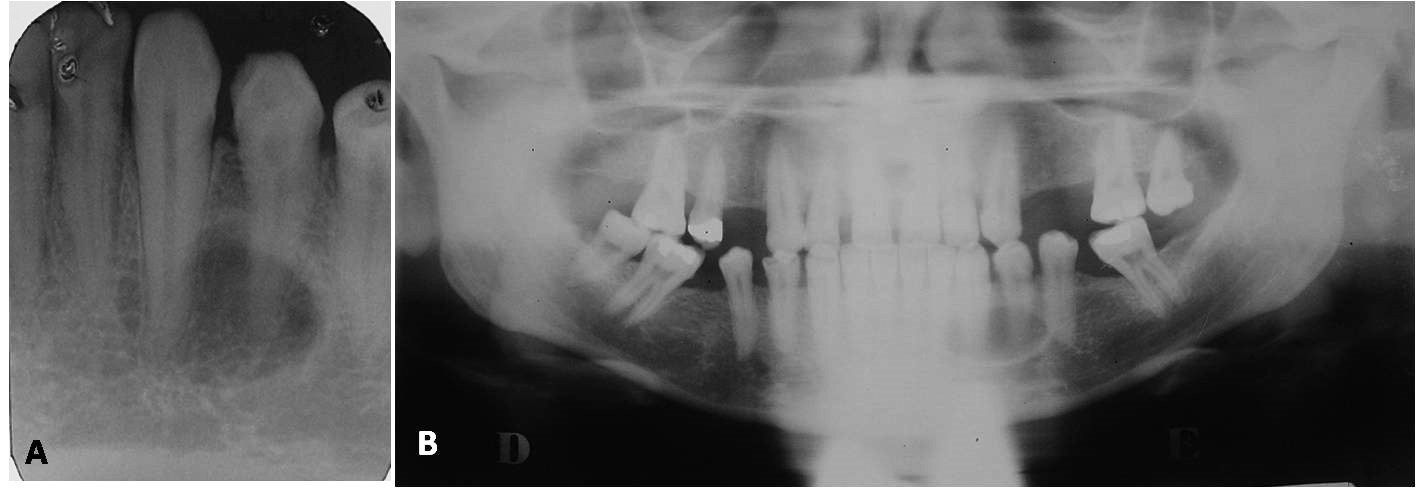

Stafne bone defects are asymptomatic lingual bone depressions of the lower jaw, frequently caused by soft tissue inclusion. The common variant of this entity affects the third molar region, below mandibular canal, and is mostly diagnosed incidentally during routine radiographic examination. The uncommon anterior variant is relatively rare and located in the premolar region of the mandible. Sublingual salivary glands are thought to be responsible for the development of this variant. The aim of this report was to describe a case of Stafne bone defect in the anterior region of mandible and a case in posterior mandible, with emphasis on clinical and radiographic findings. Dental clinicians should be aware of this entity, aiming to avoid unnecessary biopsies. In most cases, clinical and radiographic follow-up is the recommended conduct.